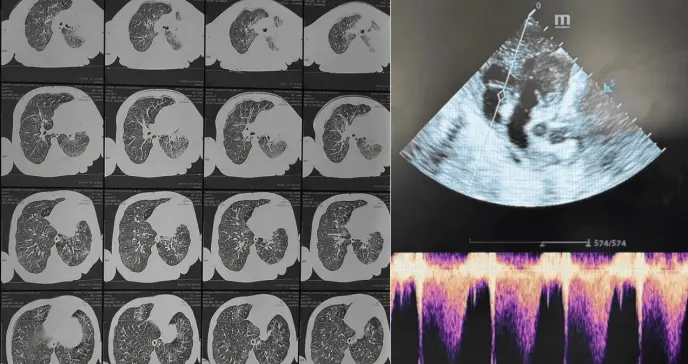

La PCR, paradójicamente normal (0.6 mg/L), no restó gravedad al cuadro. La RT-PCR confirmó la presencia de la bacteria Bordetella pertussis, y la tomografía torácica evidenció neumonía alveolointersticial con atelectasia del lóbulo medio. El hallazgo crucial llegó con la ecocardiografía: hipertensión pulmonar (PAPs 46 mmHg) sin cardiopatía estructural, secundaria a la infección.

Tomografía computarizada que revela neumonía alveolointersticial infecciosa asociada con atelectasia total del lóbulo medio.